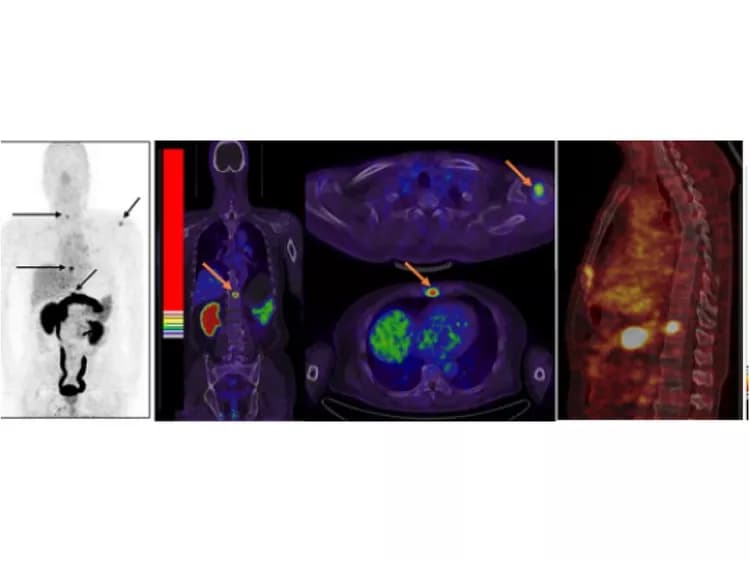

This study included 13 patients with prostate cancer (four newly diagnosed and nine post-therapy) and five healthy volunteers. Ga-68-BBN-RGD PET/CT detected 20 bone lesions in seven patients either with primary prostate cancer or after radical prostatectomy. The patients with bone metastases did not necessarily have an elevated prostate specific antigen level. "This result is better than bone scanning with MDP," Chen notes, referring to the most common radiotracer used today. "MDP bone scans are sensitive but lack specificity because localized skeletal accumulation of Tc-99m-MDP can also be observed in the case of trauma and infection." No adverse side effects were found during the whole procedure and two-week follow-up, demonstrating the safety of Ga-68-BBN-RGD.